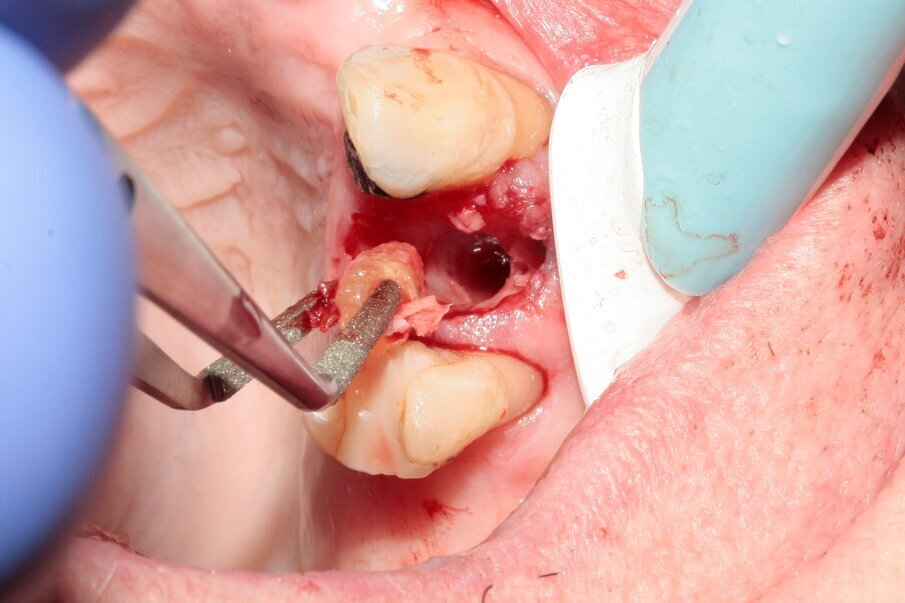

Figs. 13–15: The remains of the root were removed with the help of diamond tweezers.

By means of a gentle extraction technique, we managed to preserve the interradicular septum. Luxator P4, with its extremely sharp dual-edge blade, was used at the beginning, followed by Luxator P1 once some space had been created. Although the blades of these sophisticated instruments are reinforced with a titanium coating, they should only be used to cut the periodontal ligament and never to elevate the tooth.